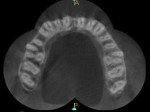

A 25-year-old male patient reported to the outpatient department with the chief complaint of pain in the left upper back region of jaw for the last 2 to 3 days. The patient also gave a history of disturbed sleep. Findings from the clinical examination revealed a deep carious lesion in the maxillary left first molar. The tooth was sensitive to percussion and elicited positive response on thermal and electric pulp testing; pain persisted even after removal of the stimulus. An intraoral periapical radiograph revealed a radiolucency approximating the pulp and periodontal ligament space widening was also present (Figure 1). On correlating the clinical and radiographic findings, a diagnosis of acute irreversible pulpitis with apical periodontitis was made and a decision to perform root canal treatment of maxillary left first molar was determined. The patient was informed about the treatment, and he provided informed consent. The patient was administered local anesthesia of 2% lidocaine containing 1:80,000 epinephrine and an access opening was performed using a rubber dam isolation. The clinical evaluation of the internal anatomy revealed 3 principal root canal systems: mesiobuccal (MB), distobuccal (DB), and palatal (P). After careful probing using a DG 16 endodontic explorer (Dentsply Sirona, dentsply.com), under 2.5X magnification using surgical loupes (Keeler Instruments, keelerusa.com), a small hemorrhagic point was noticed in a groove from the MB orifice in a palatal direction. A similar hemorrhagic point was also observed near the orifice of the main palatal canal. The conventional triangular access was modified to a trapezoidal shape to improve access to the additional canals. In both areas, there was a “catch” present with the endodontic explorer. Multiple radiographs at different angulations were not conclusive, so a multislice CBCT (Kodak, Carestream, carestreamdental.com) scan was performed of the involved tooth along with adjacent teeth. All required measures were taken to protect the patient from radiation. The images were obtained in transverse, axial, and sagittal sections of 0.5-mm thickness, which is used routinely. CBCT scan slices revealed 5 canals (2 mesiobuccal, 2 palatal, and 1 distobuccal) in the axial images at the coronal (Figure 2) and middle thirds (Figure 3). In the apical third, the palatal root had only 1 canal indicating that the 2 canals were fused between middle and apical thirds (Figure 4).